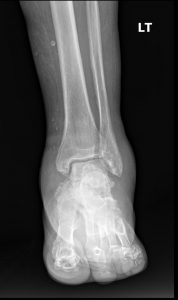

Radiographs are the workhorse for established Charcot. The classic findings are known as the “6 D’s”.

Interpreting these findings can be complex, especially in the early stages. The initial radiology report may be deceptively nonspecific, mentioning only “severe degenerative changes” or “comminuted fracture” without synthesizing these findings into the primary diagnosis of neuroarthropathy.

This is where Expert radiology consultation is critical. If the clinical picture suggests Charcot but the initial imaging is equivocal or the report is non-committal, do not hesitate to seek a Second opinion report. Specialist diagnostic imaging consultants—such as a musculoskeletal radiologist or a DACBR (Diplomate of the American Chiropractic Board of Radiology)—are trained to spot the subtle, early signs of neuropathic destruction.